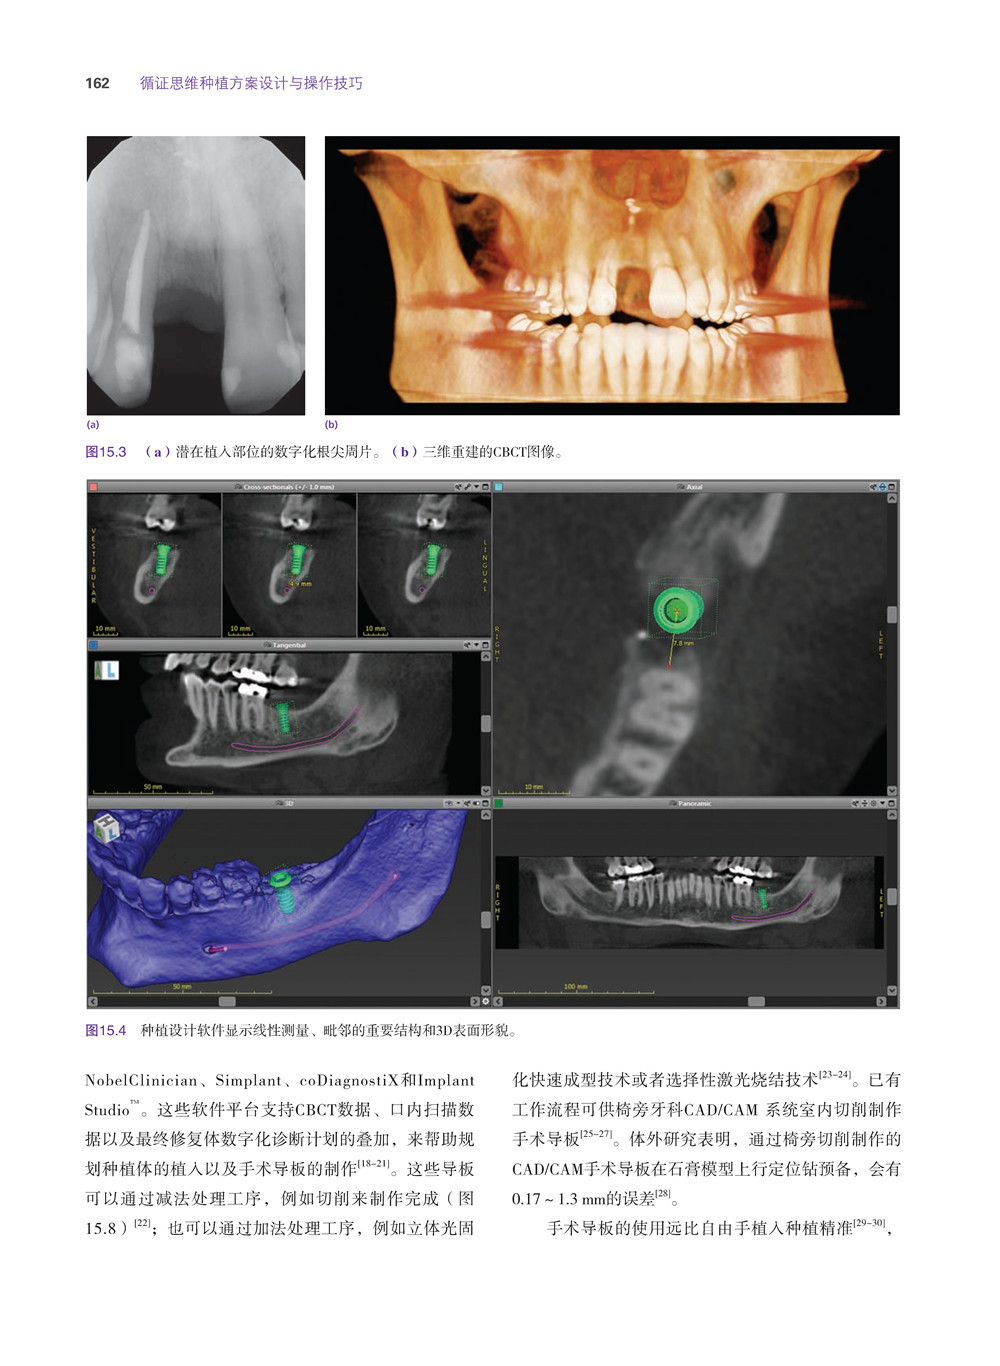

互動式CT 156

互動式電腦軟體157

手術導板157